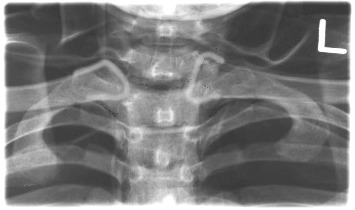

What rotation demonstrates the right SC joint open?

RAO.

What rotation demonstrates the left SC joint open?

LAO.

What indicates correct positioning on PA SC joints?

Equal distance of SC joints from vertebral column.